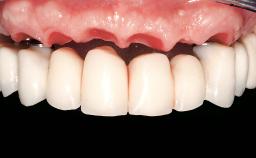

In this video Dr. Legg will demonstrate the process of utilising fully guided surgery as well as reconstruction to provide immediate full arch rehabilitation. A 56-year-old female with chronic adult periodontitis had previously undergone significant nonsurgical periodontal therapy. Unfortunately she had reached the stage where she was no longer happy with the appearance of her teeth and was suffering from increasing discomfort. A full workup was carried out in conjunction with a technical design team (at Createch). This included digital wax up of the proposed teeth, digital placement of the proposed implants and the design of the requisite surgical guides. The surgery was then carried out under sedation. The remaining upper teeth were removed, bone reduced where appropriate and the implants placed using a fully guided protocol. Following placement of screw retained abutments, the immediate provisional prosthesis was picked up in situ and passed to the technician for finishing before being fitted.

Biological Framework/Bar with appropriate contours and accessible maintenance procedures

Prosthetic volume Adequate. Space available for ideal anatomy of the restoration

Inter-occlusal space Adequate. Capable to create an anatomically & functionally correct planned restoration

Implant-supported provisional restoration Required, elevated esthetic and/or functional demands